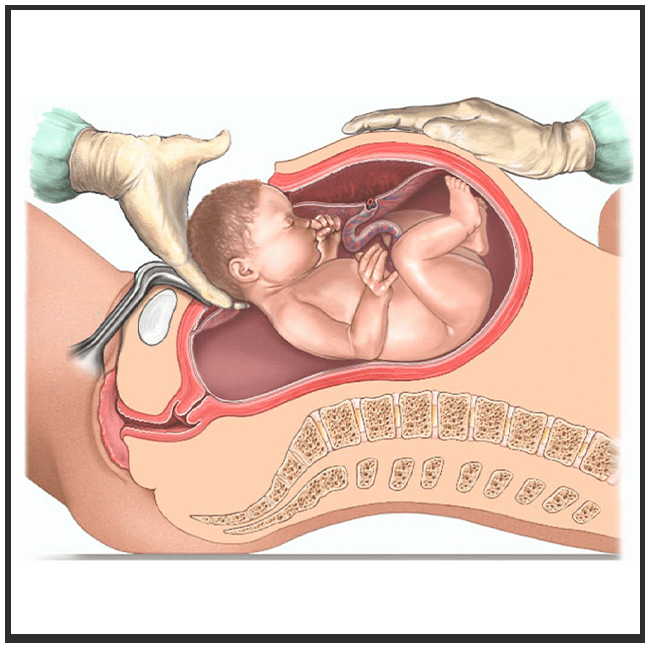

- Vaginal, assisted, and post-cesarean delivery

- الولادة الطبيعية، والمساعدة، وبعد القيصرية